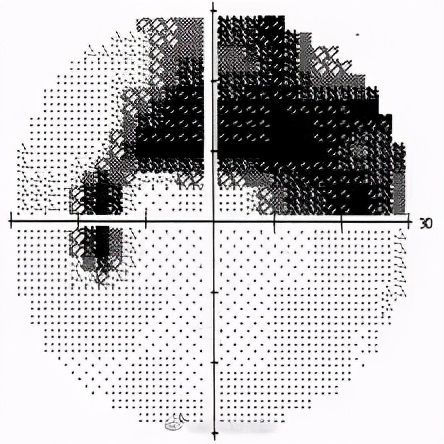

一位青光眼患者的视野检查结果

最常用的是计算机化视野测量,检测时,会要求患者将下巴放在计算机屏幕前面的一个平托上,平视正前方,机器会在患者的前方不同方位随机显现一些强弱不一的光点,当患者感觉到视野中有光闪烁时就按一下手中的按钮。测量结束时,眼科医生将得到一张患者的视野打印图。由于视野检查需要患者的理解和配合,因此结果的准确性会受到患者对检查过程的理解程度和操作的熟练程度的影响。